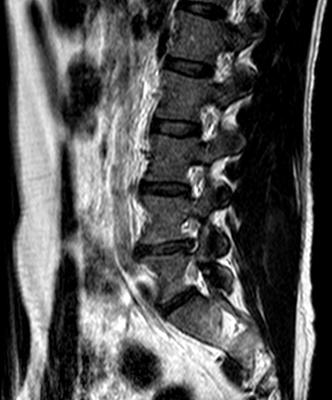

I'm not a qualified radiologist, but I do look at Xrays and scans every day and have done for 35 years. You obviously have a fairly large prolapsed disc at L4-L5, protruding into the foramen, and also compressing the thecal sac.

The scan was taken quite some time ago now (Dec 2011) and I was recently playing with the idea of obtaining a new scan, which I will probably do before visiting a chiropractor.